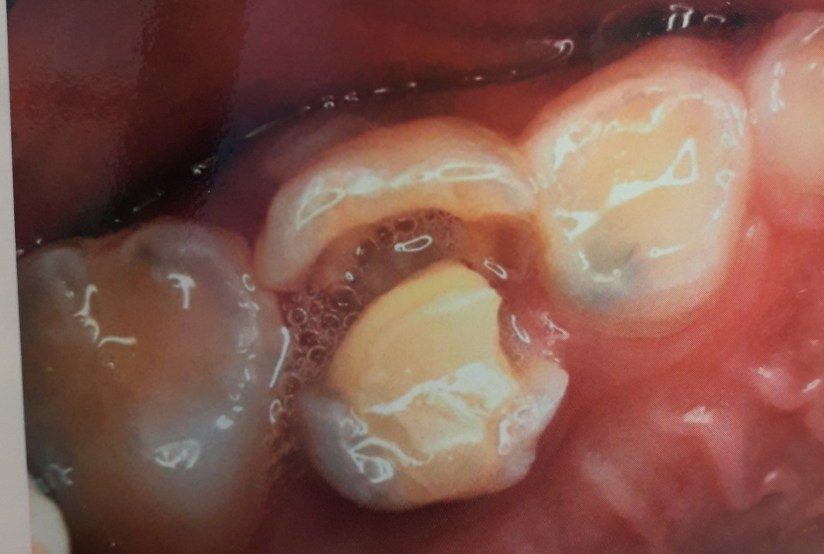

牙套, 根管治療, 乳牙小朋友乳牙牙套治療 25 二月, 2019 naomi 乳牙根管治療後未套乳牙牙套,牙齒裂開(圖牙醫公會) 上圖為根管治療完未套乳牙牙套來保護,導致牙齒斷裂需要提早拔除。 小朋友乳牙功能除了咀嚼、發音,也是為恆牙來保留空間位置。若太早拔除,鄰近的牙齒會傾倒佔據缺牙空間,未來恆牙要萌發時,會缺乏足夠位置,導致牙齒無法順利長出、位置空間不足導致牙齒排列凌亂,日後需要矯正牙齒來恢復排列。 乳牙根管治療後套上乳牙牙套 小朋友根管治療後的乳牙,若齒質不足以抵抗咬合的力量,會建議以牙套保護。或牙齒本來就有很大範圍的蛀牙,無法以樹脂或其他材料填補修復,也會建議套上乳牙牙套。 分享此文: 分享到 X(在新視窗中開啟) X 分享到 Facebook(在新視窗中開啟) Facebook 喜歡 正在載入... 發表者:naomi 檢視 naomi 的所有文章